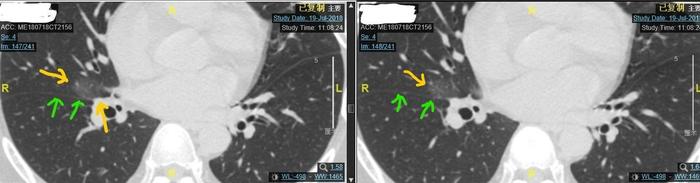

病例一、右中肺巨大磨玻璃结节

左图上边的黄色箭头指示的是磨玻璃结节,椭圆形30毫米左右。下边的黄色箭头指示的是磨玻璃结节紧贴肺动脉。两个绿色箭头指示的是中下叶交界处的肺裂。可见磨玻璃结节已经累及肺裂。

右图上边的黄色箭头指示的是磨玻璃结节,椭圆形30毫米左右,内部密度不均,有一些小空泡样改变。两个绿色箭头指示的是中下叶交界处的肺裂。可见磨玻璃结节已经累及肺裂。

病人比较年轻,磨玻璃结节影子较淡,良恶性难定。一般磨玻璃结节8毫米以上开始要3-4个月复查一次。这个人磨玻璃结节很大,如果不手术,要每2-3个月复查一次,观察结节有没有增大,内部结构有没有变化。如果这个结节是良性的,由于病人比较年轻,时间长了以后这个结节将来还会很缓慢地增大,到时候还是要手术。如果病变是恶性的,进行观察不手术,这么大的磨玻璃结节,已经侵犯肺裂了,又紧贴肺动脉,而且距离肺门较近,很容易发生淋巴结转移。而凡是侵犯肺裂的恶性肺癌术后都要化疗。所以医生和病人如果认为是良性的,观察随访不手术的话,最终病变却是恶性的话,病情可能明显发展,可能会耽误病情。

所以,最后病人做了手术。

病理是肺组织纤维增生反应,和肺泡腔内的组织细胞反应。是良性的疾病。病人不用成天提心吊胆过日子了。